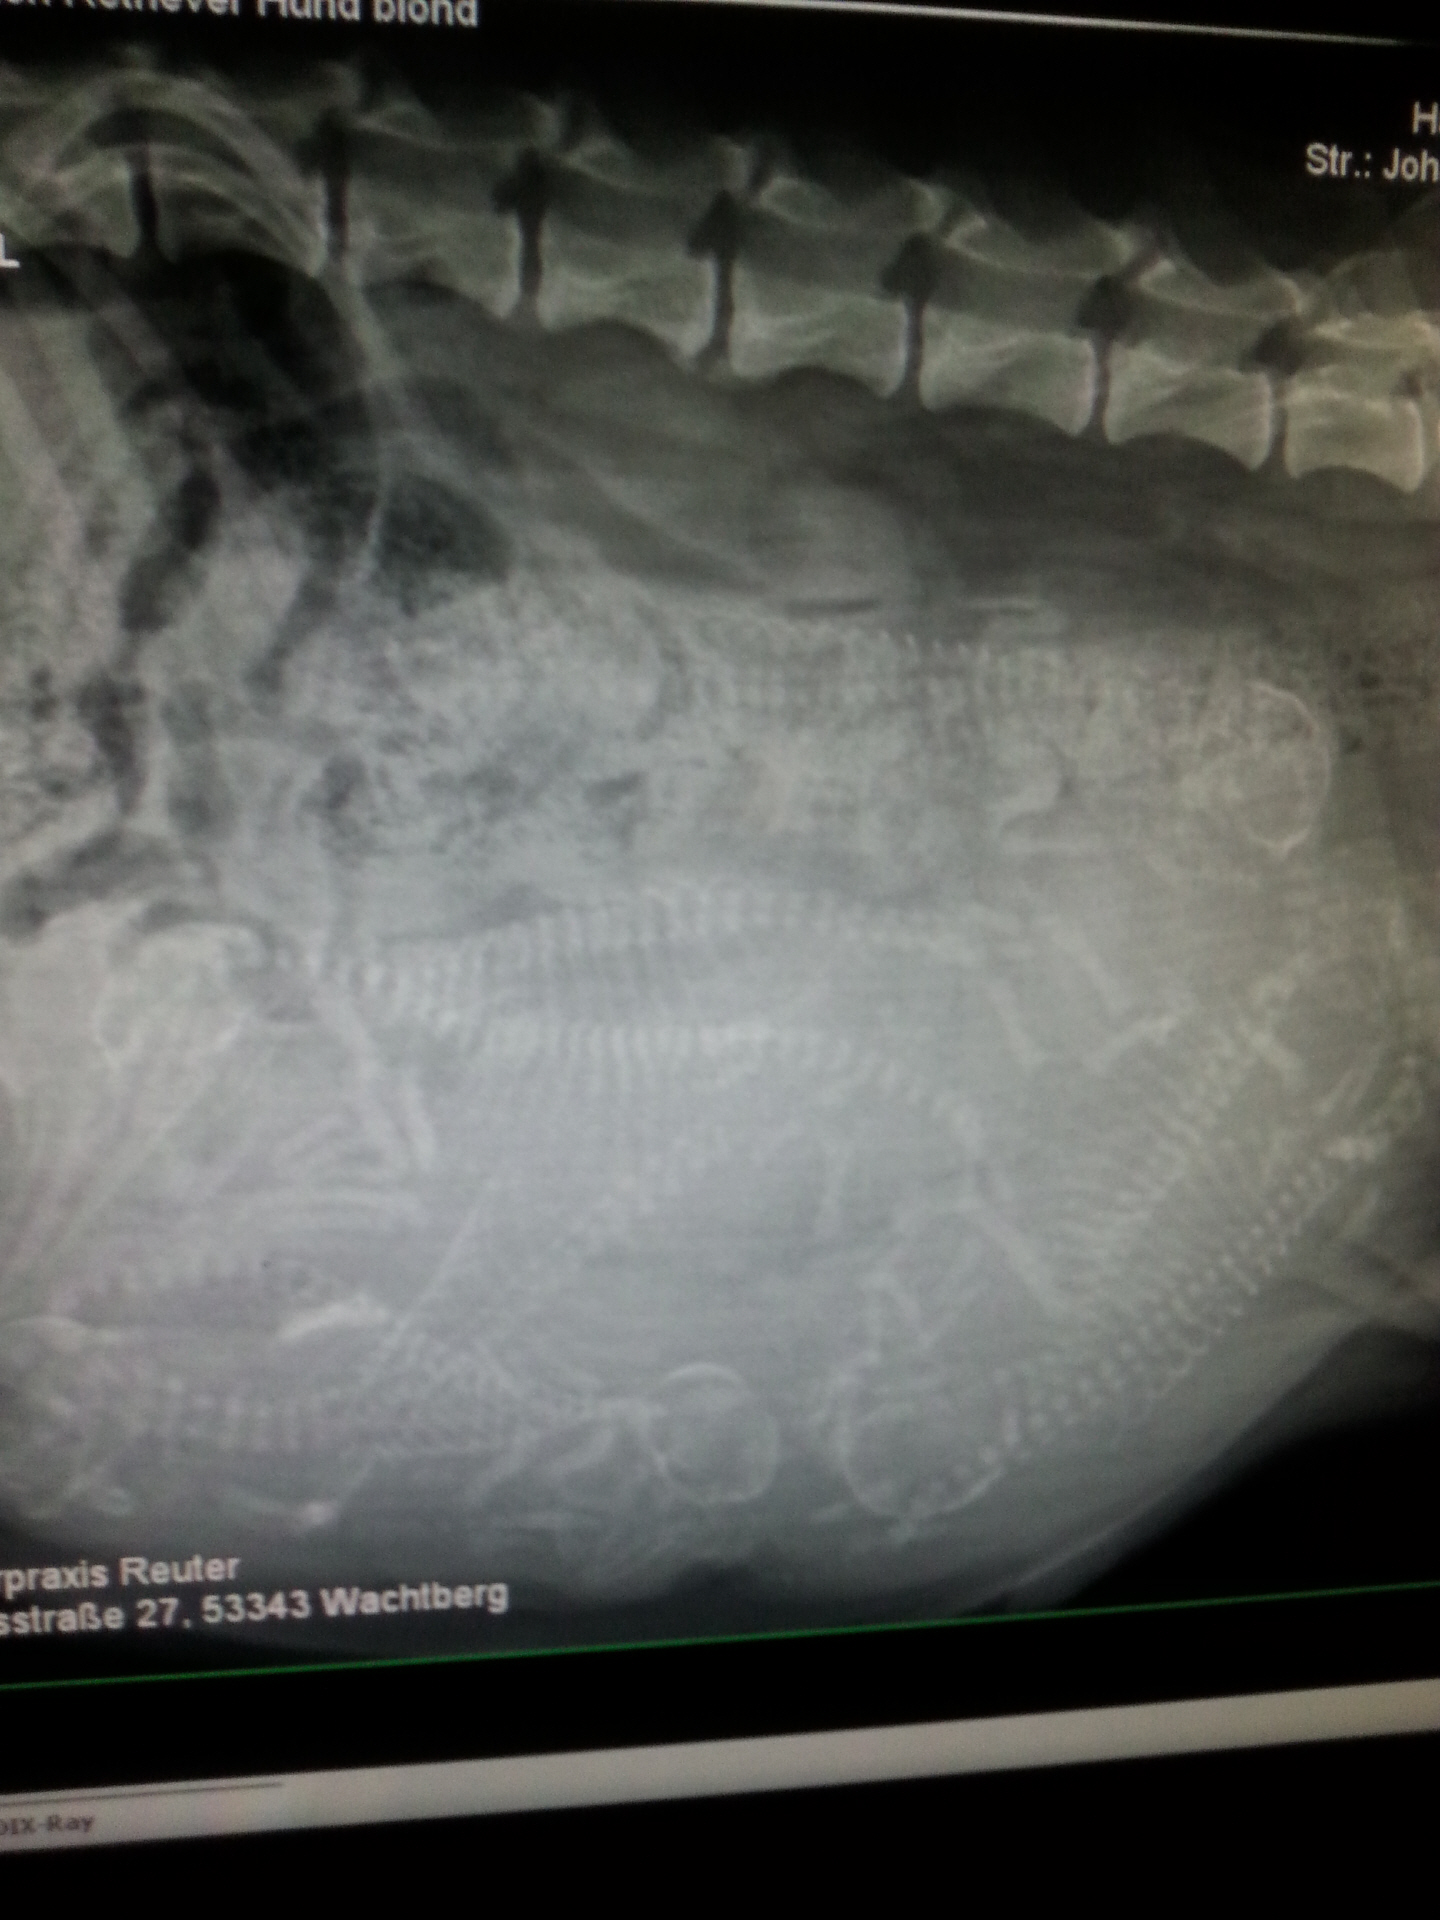

!5.09.2015

Unser F- Wurf ist unterwegs!

Das heutige Röntgen hat ergeben das Tane & Ashley Eltern werden,

wir freuen uns riesig auf die Babys!